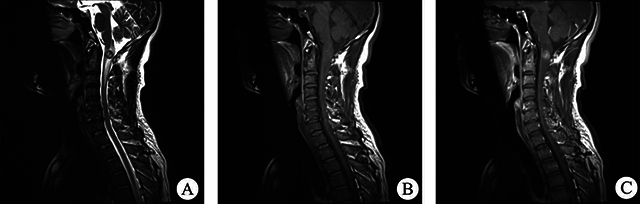

脊髓柔毛细胞星形细胞瘤(PA)是一种罕见疾病,具有不典型的临床和影像学特征,一般仅限于病例报告。我们分析了2010年1月至2021年7月期间收治的12例脊髓PA患者的临床表现、影像学结果、治疗和预后随访,并回顾了相关文献。放射学评估,尤其是磁共振成像,有助于提供有效的诊断信息。本文讨论了该疾病的诊断和鉴别方法,试图为更全面的术前评估做出贡献。

Spinal pilocytic astrocytoma (PA) is a rare disorder with atypical, clinical and imaging characteristics, and generally limited to case reports. We analysed the clinical manifestations, imaging findings, treatment and prognostic follow-up of 12 patients with spinal PA admitted from January 2010 to July 2021, and reviewed the relevant literature. Radiological assessment, especially magnetic resonance imaging, can help to provide effective diagnostic information. The diagnosis and differentiation of this disease is discussed in an attempt to contribute to a more comprehensive preoperative assessment.